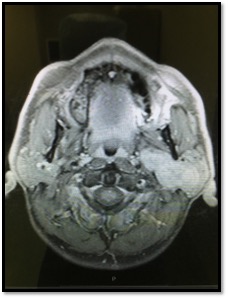

Tumori dello spazio parafaringeo: approcci chirurgici a confronto. Il video mostra due casi simili di Adenoma pleomorfo dello spazio parafaringeo studiati preoperatoriamente con Risonanza Magnetica. L’approccio scelto, come nella maggioranza dei casi, è stato esterno per via parotido cervicale. La differenza fra i due casi è stata la preservazione del tessuto ghiandolare parotideo nel secondo caso.

Reperito il tronco principale del VII ed isolato completamente il nervo facciale, nel primo caso è stata effettuata una parotidectomia superficale e successivamente l’asportazione del lobo profondo sottofacciale. Il nervo, completamente isolato e disseccato in tutti i suoi rami, è stato delicatamente sollevato con loop elastiche permettendo l’accesso allo spazio parafaringeo. Il tumore occupante lo spazio parafaringeo è stato agevolmente dissecato con manovra digitale ed asportato integralmente con un piccolo strato di tessuto parotideo profondo adeso. Il campo operatorio al termine dell’intervento evidenzia la asportazione completa del tessuto parotideo (parotidectomia totale) e la conservazione integrale di tutti i rami del nervo facciale perfettamente funzionanti al termine della procedura chirurgica.

Nel secondo caso, si è eseguita la ricerca e dissezione del nervo facciale nei rami inferiori, sollevando senza asportarlo il lobo parotideo superficiale. L’ accesso allo spazio parafaringeo, altrettanto agevole, è avvenuto sollevando delicatamente con loop elastiche il ramo inferiore del VII verso l’alto ed approciando il tumore sotto il lobo parotideo profondo, senza asportare il tessuto ghiandolare. La dissezione dell’adenoma è avvenuta con manovra digitale alla cieca come nel primo caso, ottenendo la stessa radicalità .